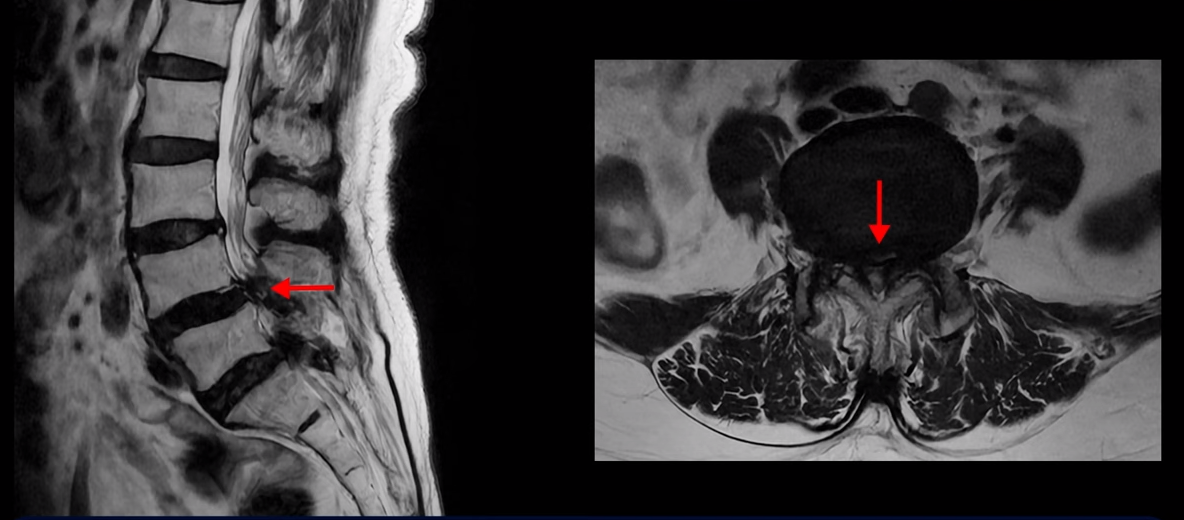

먼저 이분 MRI를 보면서 자세히 설명 드리겠습니다. 보시다시피 허리 여러 마디가 안 좋습니다.

특히 4번 5번에는 심한 중심성 협착이 있어 척추관이 매우 좁아져 있습니다.

5번 1번도 척추관이 좁아져 있고 특히 좌우 신경이 빠져나가는 추간공이 좁아져 있는데 5번 1번 왼쪽 추간공은 많이 좁아져서 신경이 눌리고 있습니다.

그래서 이 환자분은 허리도 아프지만 양쪽 엉덩이가 저리고 아프며 양쪽 다리가 무거워서 걷기가 어렵고 양쪽 발바닥까지 자갈을 밟는 것 같은 감각 이상이 있습니다. 신경이 많이 눌리니까 양쪽 다리에 힘이 없어 작년부터 지팡이를 짚으셨는데요. 우리나라 최상급 대학병원에서도 고령이시고 여러 마디가 안 좋으시니 큰 수술을 받는 것보다 그냥 조심하면서 참고 사시는 게 더 낫다고 말씀을 들었습니다.

그런데도 아직도 많은 분들이 근육의 중요성을 모르고 신경치료만 하고 있습니다. 하지만 근육과 신경은 떼놓고 생각할 수가 없습니다. 근육이 나빠지면 신경 눌림이 심해져서 협착증 증상이 더 악화되고, 또 신경이 눌리면 근육도 더 빨리 나빠집니다. 반대로 근육이 좋아지면 신경 눌림이 줄어들고 협착증이 좋아집니다. 신경이 눌린다고 하니까 신경 눌림을 풀어주는 수술만 생각을 하시는 분들이 많은데 근육이 좋아져서 허리를 잘 지지해주면 신경이 덜 눌립니다. 이 환자분도 근육이 얼마나 안 좋은 지는 이분 척추가 얼마나 휘어있는 지만 봐도 알 수 있습니다. 보시다시피 근육들이 척추를 잘 지지하지 못하니까 척추가 심하게 휘어있습니다.